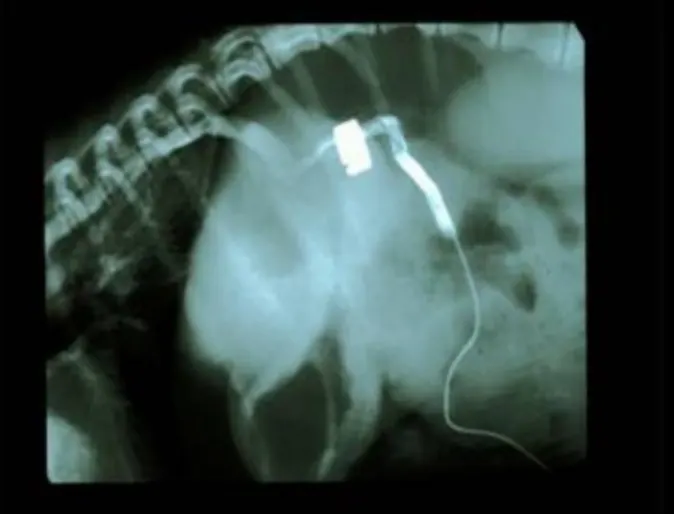

Several diagnostic tests may be performed to support the diagnosis of a portosystemic shunt, including blood tests, urinalysis, and imaging tests. X-ray, ultrasound, portograms ( a dye study that images blood vessels to the liver, Figure 2) or nuclear scintigraphy (a nuclear scan that measures liver blood flow) are all often used in the diagnosis of portosystemic shunts. Even with all of these tests, surgery may still be required to confirm the diagnosis.

Figure 2: Portogram - an injection of dye into the portal system (blood supply to the liver) illustrating the appearance of a portosystemic shunt. This shunt has had an ameroid ring placed around it.